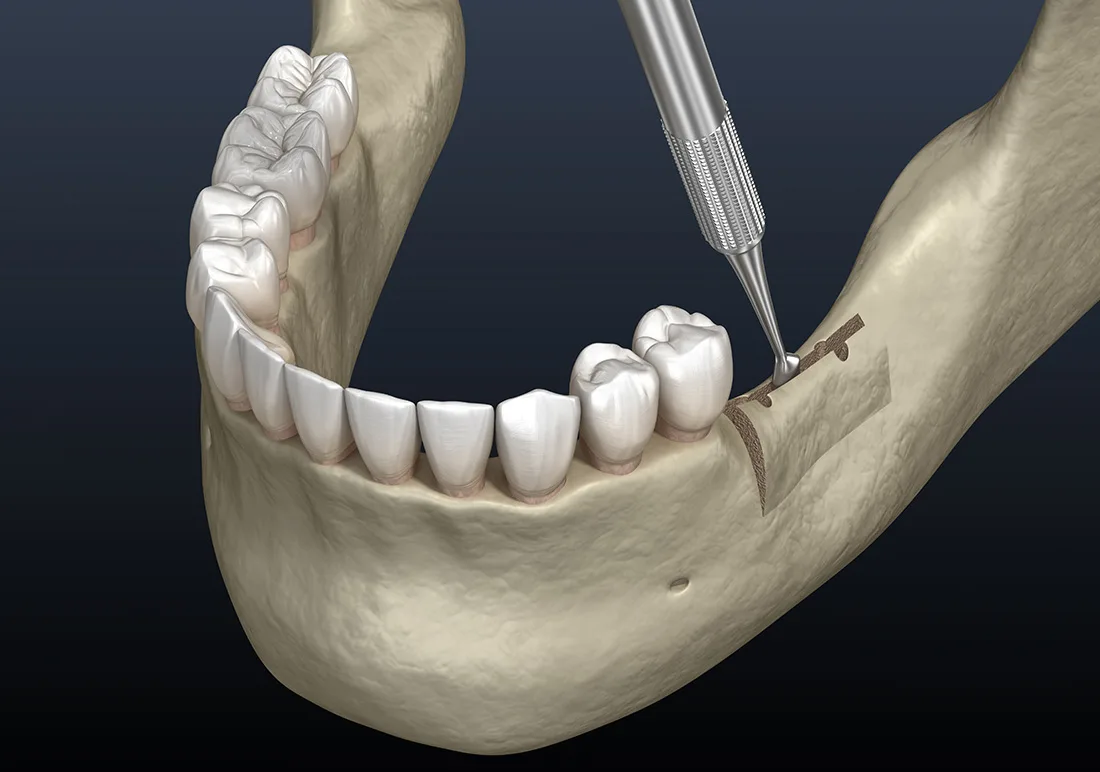

If you’ve struggled from jaw bone loss due to missing teeth, you’re not alone, and there’s a solution to get you smiling again. A ridge augmentation recreates the natural contour of the gums and jaw bone, restoring its form and creating a solid foundation for implants.

After tooth extraction, the jaw bone may need to be rebuilt and reshaped to make sure that your mouth can accommodate a dental implant, or for aesthetic purposes. Not everyone needs ridge augmentation, but it’s often done immediately after tooth extraction to avoid the need for another surgery. If your oral surgeon believes that your jaw bone may need strengthening, it’s a good idea to get ridge augmentation during your tooth extraction procedure.